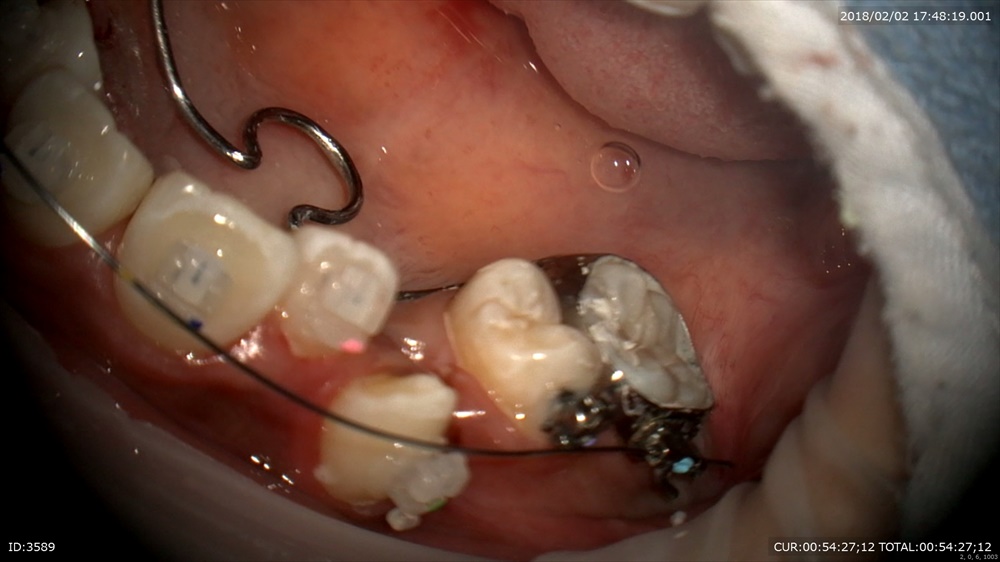

矯正から。今日が装置装着の初日。当院は通常分ける作業を1日で、すべてやります。抜歯→TPA装着→DBS→ワイヤー装着

TPA装着、DBS

デーモンシステム。こうする事で矯正期間の短縮と痛みの軽減につながります。綺麗になるのを楽しみに!!